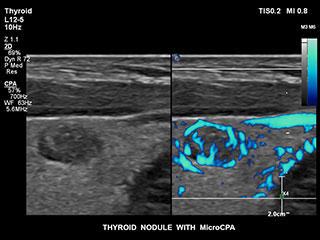

Получение информации о кровотоке в мелких сосудистых структурах с небольшим кровотоком традиционно считается сложной задачей. Благодаря новой функции MicroCPA в системе EPIQ визуализация капиллярного кровообращения с низкой скоростью кровотока выполняется быстро и просто, обеспечивая более точную диагностику при оценке перфузии органов и сети небольших сосудов.